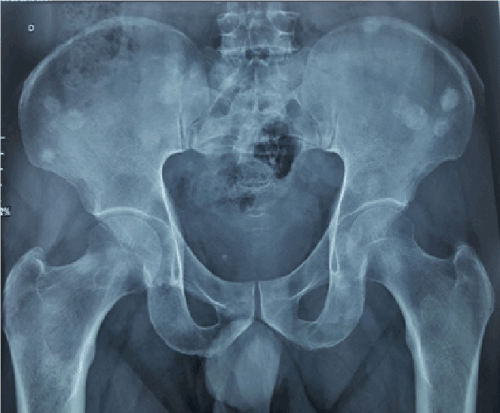

A 63 years old man with history of diabetes and hypertension, presented for bone pain. Pelvic X Ray showed multiple osteoconsensant lesions of the iliac wings, the sacrum and the femurs (Figure 1). CT scan objectified multiple hepatic metastases with a laterorectal mass (Figure 2). Colonoscopy showed aspect of extrinsic compression. Endoscopic ultrasound objectified a rectal mucosal lesion of 5x3,5 centimeters appearing in contact with the prostate (Figure 3) [1-5]. Histologically, hepatic biopsy confirmed a tumor proliferation that was made of two architectural aspects independent cells, and trabeculolobular classical endocrine architecture with expression of synaptophysin on immunochemistry [1-5] (Figure 4).

Figure 3. Endoscopic ultrasound objectified a rectal mucosal lesion of 5x3,5 centimeters appearing in contact with the prostate